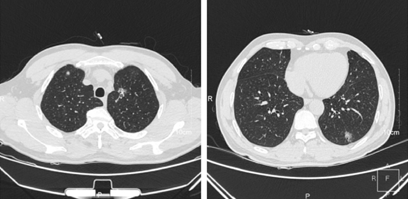

左左肺下叶浸润性腺癌,病灶呈现出不规则GGN表现,边界清晰,有毛刺和分叶征

右左肺上叶前段浸润性腺癌,轴位示不规则GGN表现,边界清晰,有分叶和胸膜凹陷征